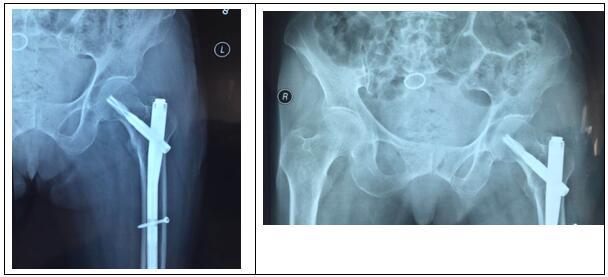

圖片三:(術(shù)后照片)

科主任楊志奎帶領(lǐng)曹熙、田濤、安蒙蒙、張凱迪醫(yī)師,經(jīng)充分討論,考慮到患者高齡,合并高血壓、冠心病等多種基礎(chǔ)疾病。自身恢復(fù)能力不強(qiáng),身體機(jī)能較差,已承擔(dān)不起傳統(tǒng)開放性手術(shù)所帶來的創(chuàng)傷。為改善患者生活質(zhì)量,再次站立起來,根據(jù)骨折類型,為老人選擇行閉合復(fù)位股骨近端骨折PFNA髓內(nèi)內(nèi)固定方式。手術(shù)時長約35分鐘,術(shù)中透視骨折復(fù)位滿意,內(nèi)固定裝置位置適當(dāng)。術(shù)后第1天,即指導(dǎo)患者行左髖、膝關(guān)節(jié)屈伸活動鍛煉,術(shù)后第2天可坐起。

老年股骨粗隆間骨折患者,常常導(dǎo)致患者長期臥床,嚴(yán)重影響患者生活質(zhì)量及生命安全,保守治療很容易引發(fā)尿路感染、肺部感染、褥瘡、深靜脈血栓等一系列并發(fā)癥,嚴(yán)重者可導(dǎo)致生命意外。一般在身體條件允許下均建議早期行手術(shù)治療。手術(shù)治療有開放復(fù)位鋼板內(nèi)固定及閉合復(fù)位PFNA髓內(nèi)內(nèi)固定手術(shù),相比較,PFNA髓內(nèi)內(nèi)固定手術(shù)其術(shù)區(qū)創(chuàng)傷更小、疼痛感更輕、恢復(fù)更快,早期活動度明顯加大,大大減少了臥床并發(fā)癥發(fā)生率。